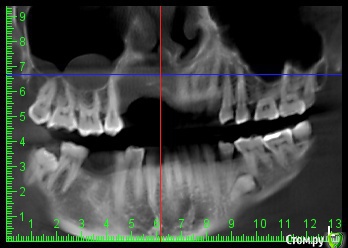

L.E.S.I.K. Опубликовано 13 июля, 2017 Поделиться Опубликовано 13 июля, 2017 Доброго времени суток, коллеги. Пациент обратился с желанием иметь несъемную конструкцию на имплантах. В анамнезе 5 мес назад операция по поводу хронического одонтогенного остеомиелита верхней челюсти. В настоящее время клинический признаков воспаления нет. Есть только значительный дефект. 3 класса по Зиберту. Какие возможны методы аугментации кости в объеме необходимом для имплантации? Мне на ум приходит только блоки из подвздошной Ссылка на комментарий

Bier Опубликовано 13 июля, 2017 Поделиться Опубликовано 13 июля, 2017 плохие очень снимки, толком ничего не понятно. Блоки с подвздошки забудьте, они резорбируются быстро. Тут нужен один из вариантов GBR Покажите нормальные срезы, чтобы был ясен уровень костных пиков на соседних зубах. Ссылка на комментарий

L.E.S.I.K. Опубликовано 13 июля, 2017 Автор Поделиться Опубликовано 13 июля, 2017 Возле 21 пик есть, а в обл 25 снижен, корень оголен на четверть. Смущает также отсутствие местами костно дна полости носа Ссылка на комментарий